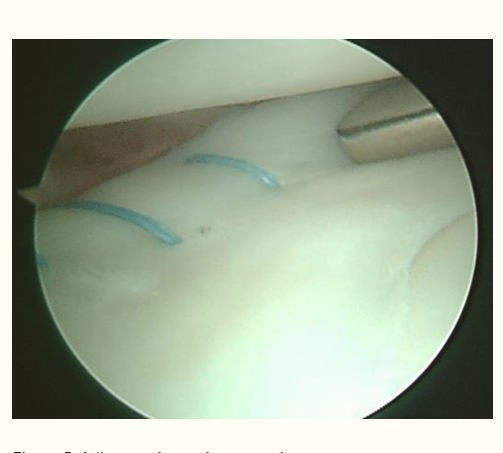

The knee joint is designed to bend up and down and rotate to a certain degree. If something gets caught inside the joint, it blocks the movement and the knee gets lock. The locked knee is most commonly as a result of a meniscus tear. Other causes of a locked knee are due to cartilage and bony fragments, ligament injury, loose tissue fragment and patella (knee cap) dislocation. In this article, I would like to focus on the meniscus injury as it is the most common cause of locked knee.

The meniscus is a rubbery, C-shaped cartilage in between the femur (thighbone) and tibia (shinbone). There are two menisci in each knee joint, the inner medial meniscus and the outer lateral meniscus. The outer edges are fairly thick while the inner surfaces are thin. The meniscus provides smooth knee motion, stability and contributes to a healthy knee through its shock absorber effect. During the various phases of the walking cycle, forces shift from one meniscus to the other, and forces on the knee can increase to 2 – 4 times body weight. While running, these forces on the knee increase up to 6 – 8 times body weight. There are even higher forces when landing from a jump.